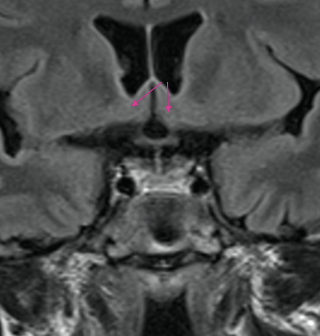

What is indicated by the arrows?

Hypothalamus